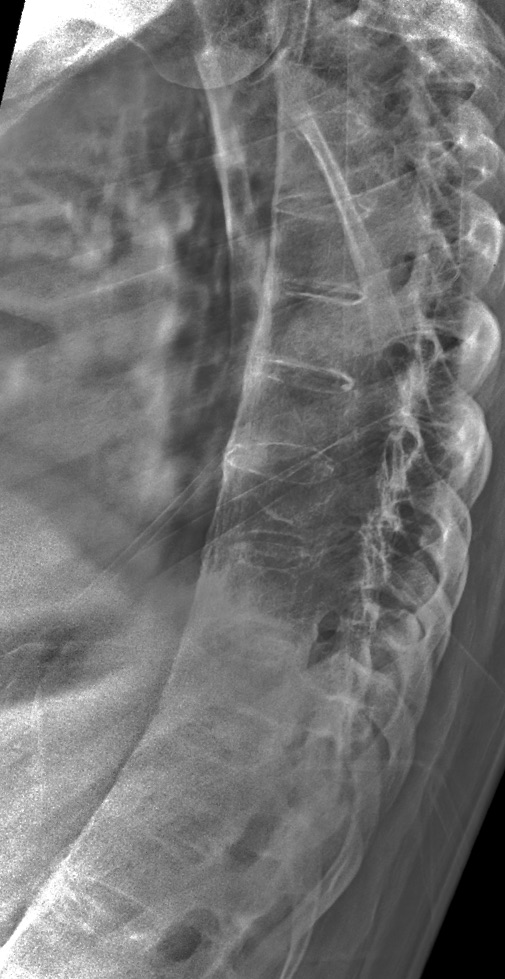

This is Leigh today, 35 years after the initial diagnosis

These are Leigh’s most recent X-rays